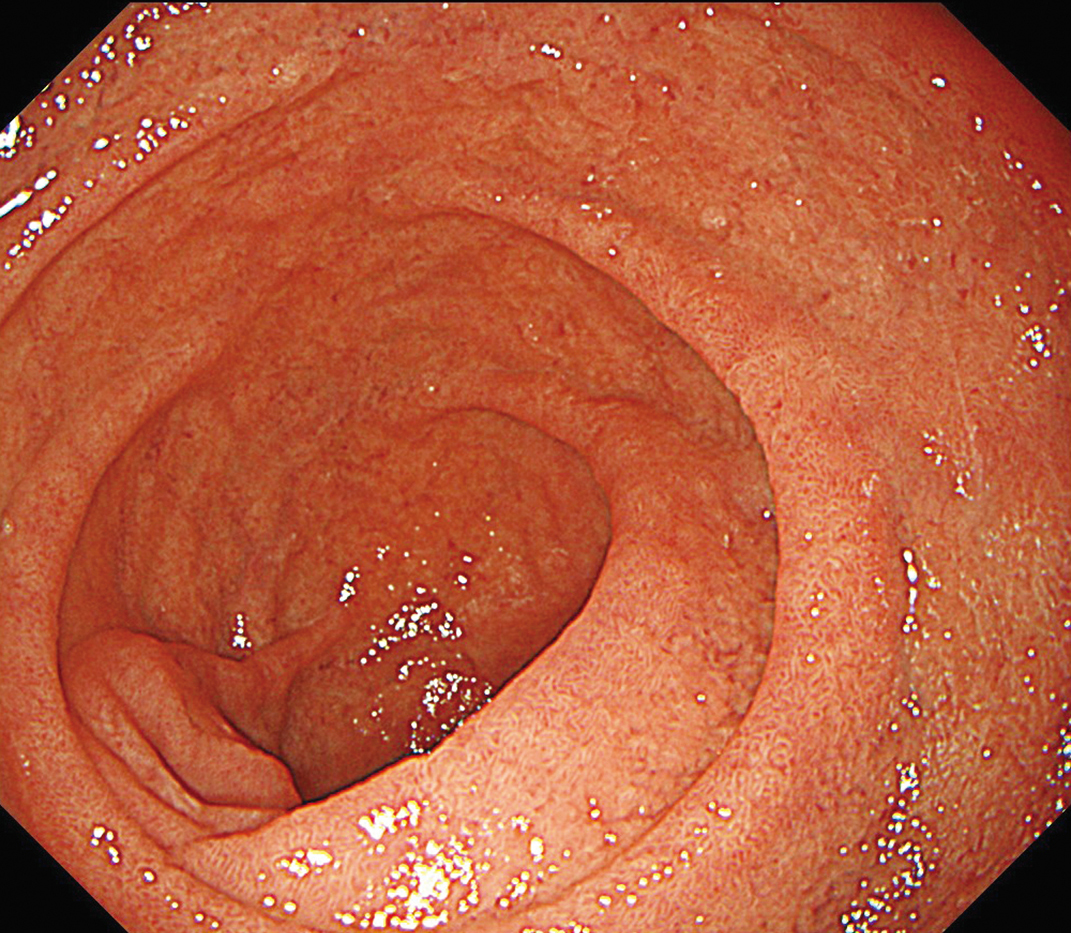

EVIS X1×GIF-1200N 症例画像

下部食道